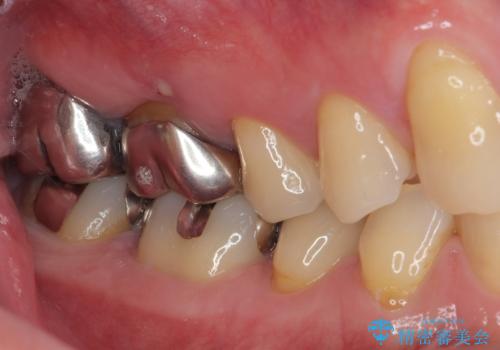

- 右下の銀歯が取れたとのことで来院された患者様です。以前にも取れていたところで、メタルインレーの不適合も認めていたため、次回外れたらオールセラミッククラウンにやり替えていくことを説明していたため、オールセラミッククラウンによる補綴治療を行っていくことにしました。

拡大鏡視野下で虫歯を除去しオールセラミッククラウンに適した形に整えました。

歯と歯茎の間に圧排糸と言われる糸を入れてシリコーン印象材にて型どりをしました。